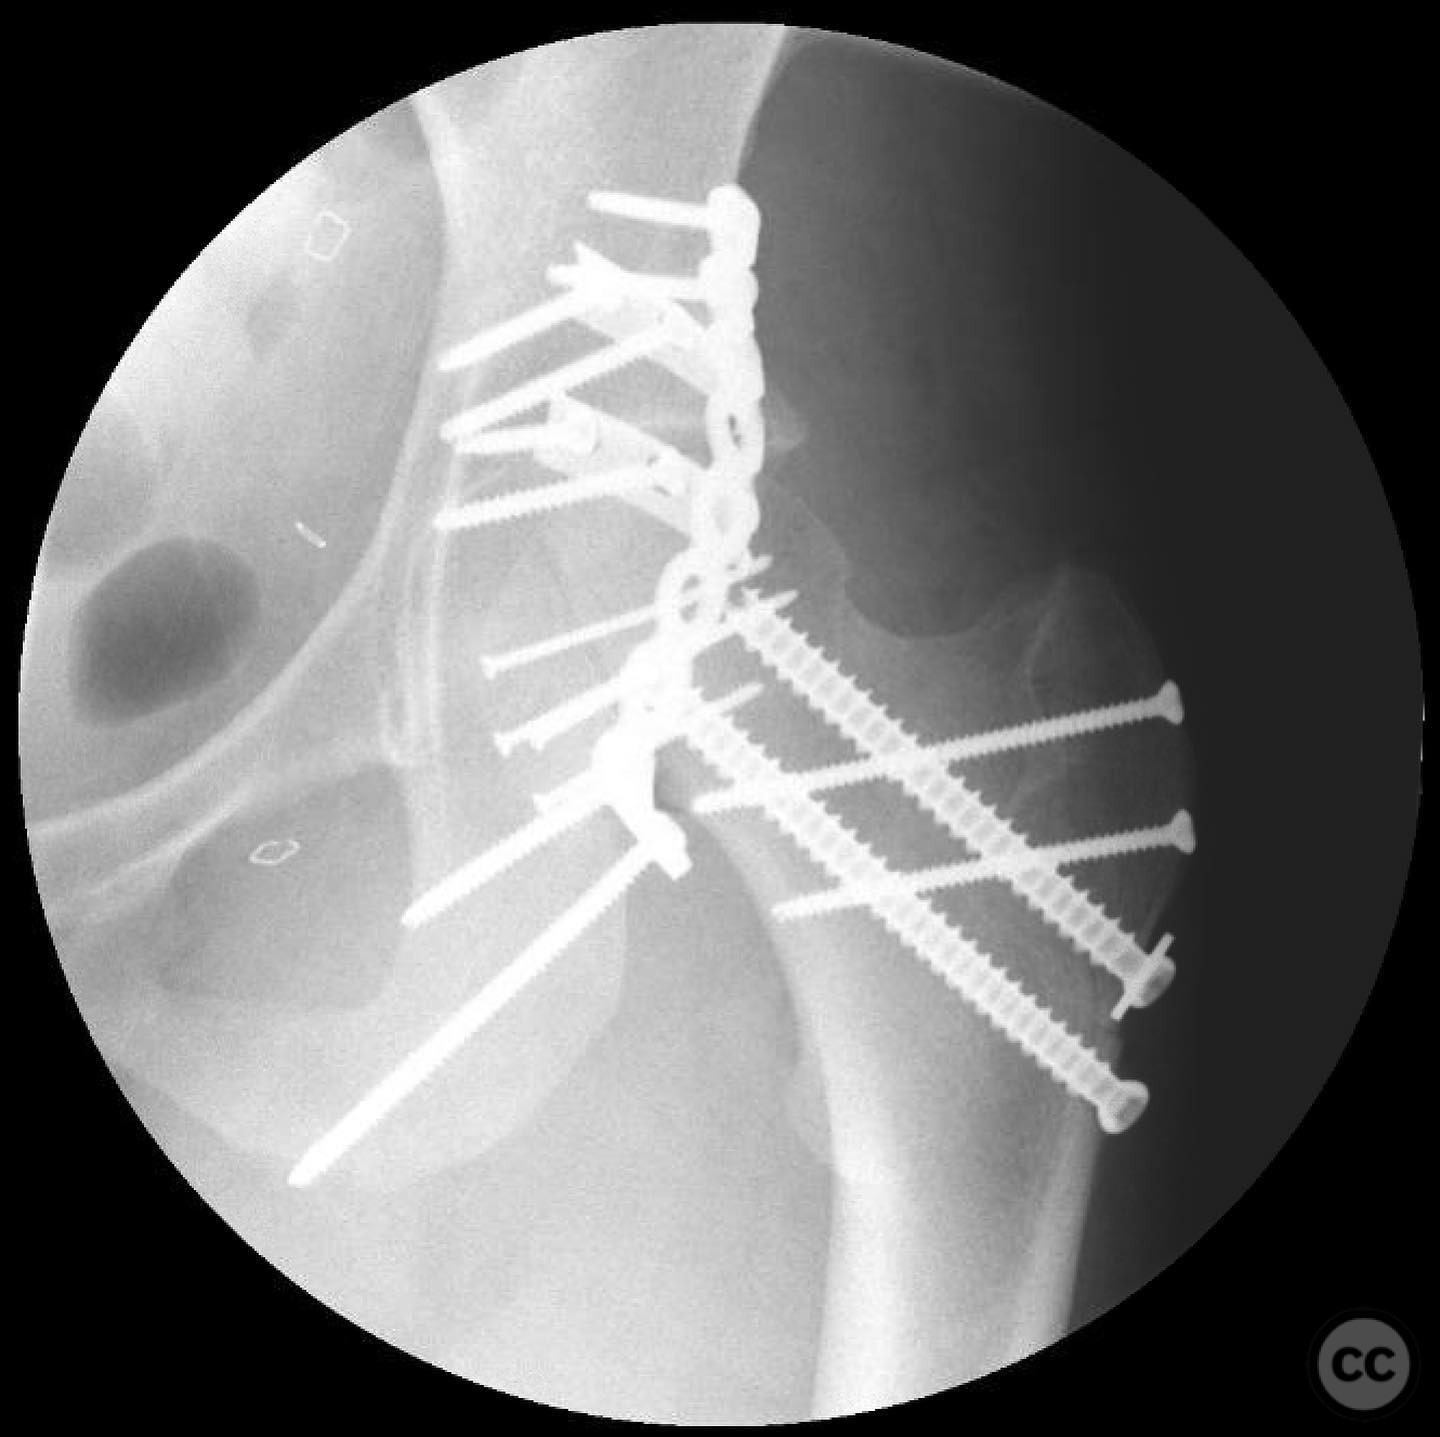

The femoral head defect required meticulous reconstruction using a femoral head allograft to restore its round shape. The posterior wall instability was addressed with spring plates and three suture anchors to reattach the capsulolabral complex. The reconstruction aimed to achieve a stable and congruent hip joint.

Orthopaedic implants used:   Femoral head allograft, spring plates, suture anchors.